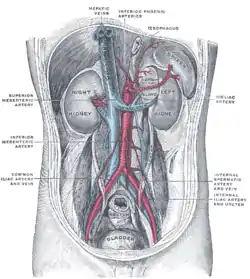

Ramificándose desde la aorta a la altura de la parte superior de la vértebra L1 (o primera lumbar), por debajo del diafragma, en los seres humanos, es una de tres ramas que desde la línea media se proyectan hacia adelante —las otras dos son la mesentérica superior y la mesentérica inferior—. Ocupa el centro de la denominada región celíaca.

Distribución

La arteria celíaca proporciona sangre oxigenada al hígado, estómago, parte abdominal del esófago, bazo y la mitad superior del duodeno y del páncreas. Estas estructuras corresponden al intestino proximal embrionario. (De igual modo, las arterias mesentérica superior y mesentérica inferior irrigan estructuras que se desarrollaron del intestino medio e intestino distal, respectivamente. Nótese que estas tres ramas anteriores de la aorta abdominal son diferentes y no pueden sustituirse, aunque existen conexiones limitadas entre sus ramas terminales).

La arteria celíaca es una fuente de sangre esencial, ya que las interconexiones con las demás arterias principales del intestino no son suficientes para mantener una adecuada perfusión. Por lo tanto no puede ligarse en una persona viva durante la cirugía, y la obstrucción de la arteria celíaca produce necrosis de las estructuras que irriga.

Retorno venoso

La arteria celíaca es la única de las arterias principales que nutren los órganos digestivos que no tiene una vena de nombre similar.

La mayor parte del retorno procedente de los órganos digestivos (incluyendo la zona de distribución de la arteria celíaca) es desviado hacia el hígado por medio del sistema venoso portal para posterior proceso y detoxificación en el hígado antes de volver a la circulación sistémica a través de las venas hepáticas.

En contraste con el retorno desde estructuras procedentes del intestino medio e intestino distal embrionarios, respectivamente, el retorno venoso desde la arteria celíaca pasa, bien a través de la vena esplénica, que vacía su contenido en la vena porta hepática, o bien a través de pequeñas venas tributarias del sistema venoso portal.

Por la vena esplénica se transporta bilirrubina (el producto de desecho del metabolismo de la hemoglobina) hacia el hígado para su excrección por el conducto biliar.